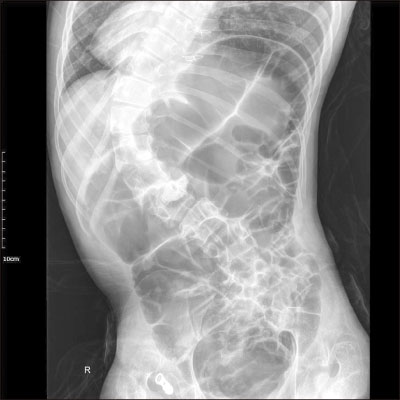

Fig. 3). Proximal transverse colon was redundant and upstream dilatation from the twisted transverse colon to the ascending colon and the cecum was found with reversed intestinal anatomy, as identified on preoperative images. Sigmoid colon was collapsed and not redundant, so the suspicious sites of endoscopy were not related to the symptoms. Adhesiolysis and fibrous band lysis between the transverse colon and adherent soft tissue was done. Redundant proximal transverse colon was resected via mini-laparotomy site, and end-to-end colocolic anastomosis was performed (

Fig. 4). There was no postoperative event, and the patient was discharged without complications.

Fig. 4Resected redundant transverse colon.